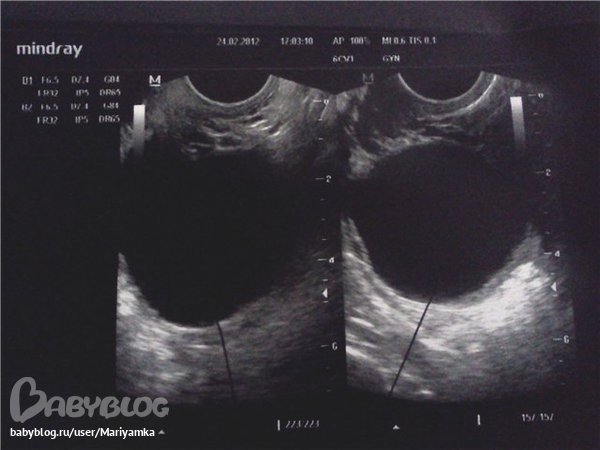

23-24.02.2012 (17,18 дни цикла) вердикт УЗИ фолликулярная киста